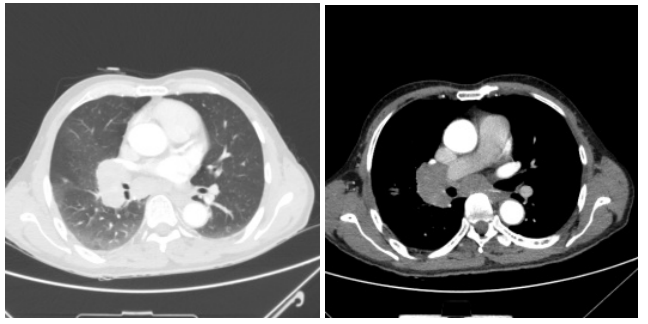

患者王某某,男,66岁,半年前出现咳嗽乏力。入院后,行胸部CT平扫+增强检查,结果显示患者右侧肺门区约5.2cm×3.3cm软组织肿块影,边缘毛糙,增强扫描呈明显强化,包绕右肺动脉干及其分支。根据CT检查结果,呼吸内科医生与家属商量后决定为患者行电子支气管镜检查,以尽快明确病因。